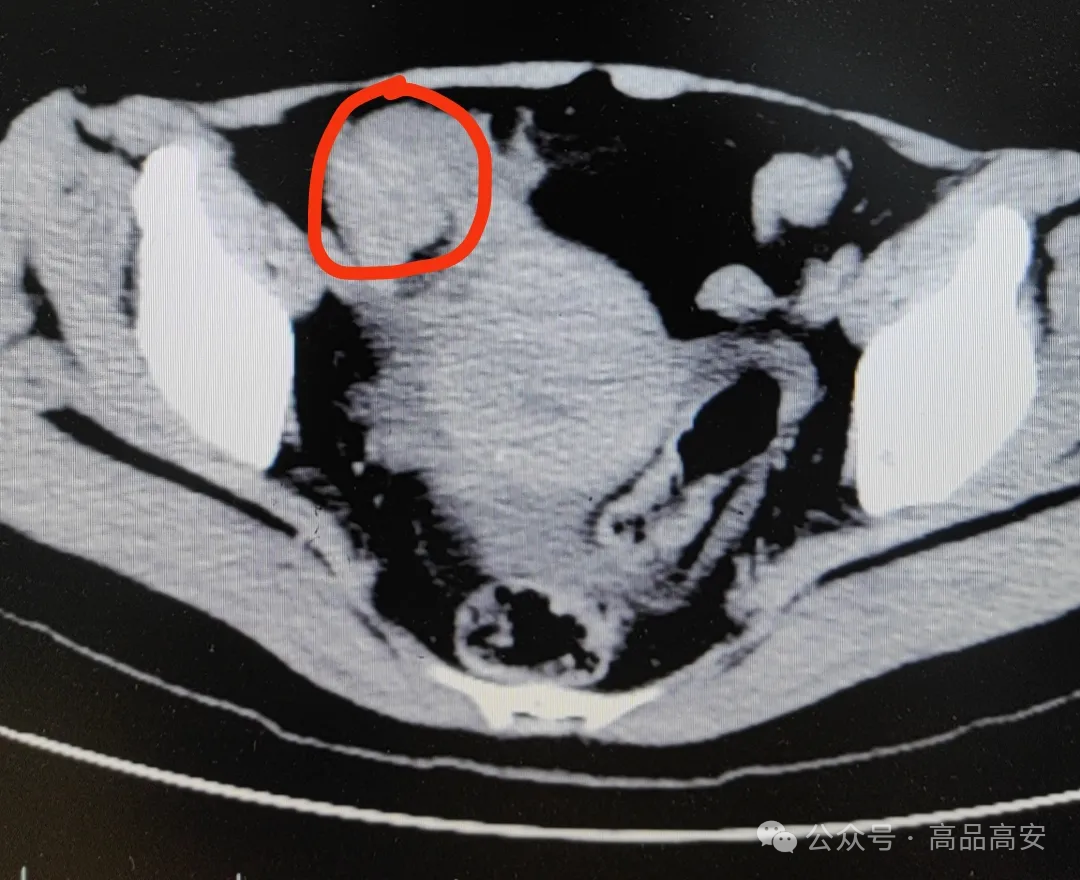

医生高度怀疑冯女士患上了绞窄性肠梗阻。最终手术从她肠子里切出一堆“石头”,也就是“柿石症”,最大的直径达4公分!